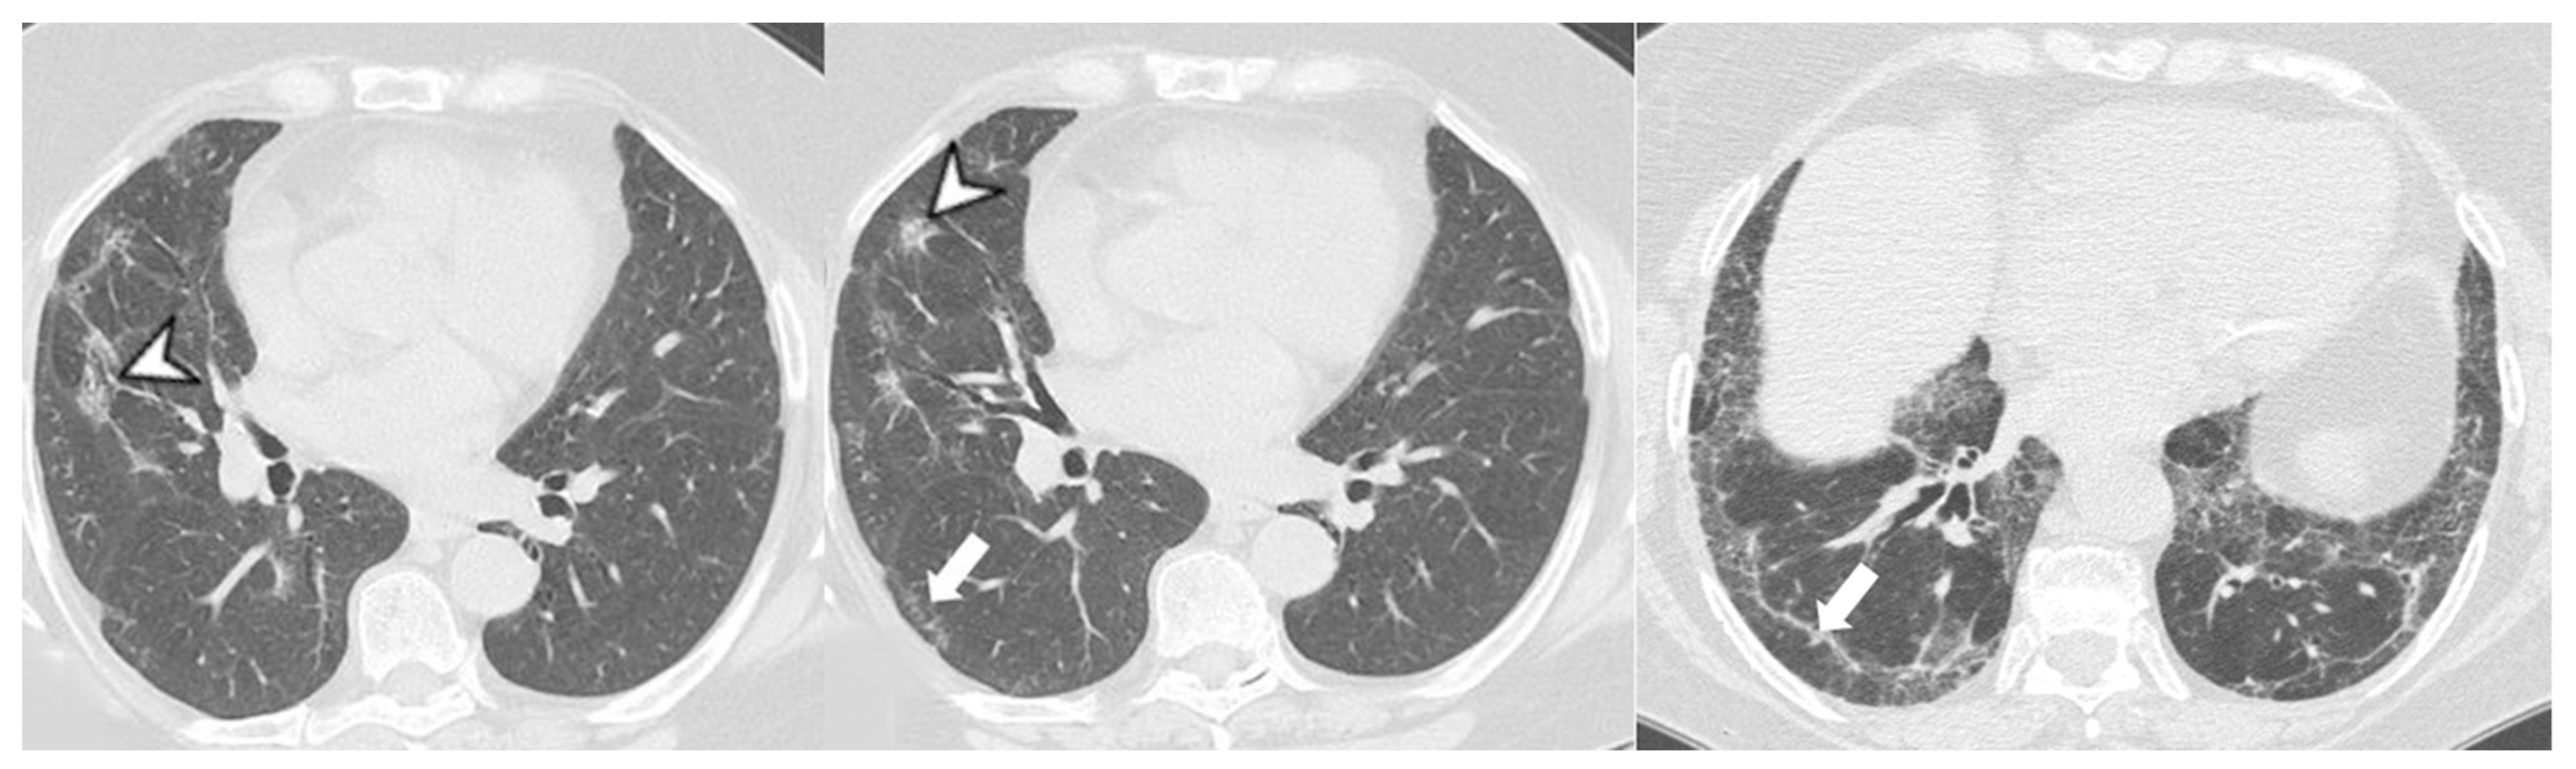

4.2.1. HRCT Findings of Patients with Anti-ARS Abs

- Waseda, Y.; Johkoh, T.; Egashira, R.; Sumikawa, H.; Saeki, K.; Watanabe, S.; Matsunuma, R.; Takato, H.; Ichikawa, Y.; Hamaguchi, Y.; et al. Antisynthetase syndrome: Pulmonary computed tomography findings of adult patients with antibodies to aminoacyl-tRNA synthetases. Eur. J. Radiol. 2016, 85, 1421–1426. [Google Scholar] [CrossRef]

| Lesions | GGO, reticulations, consolidations | consolidations, GGOs | |

| Distribution | Homogeneous; lower lung lobes, along bronchovascular bundles and lung periphery; loss of volume of lower lobes | Patchy; peripheral lower lobes or along the bronchovascular bundles | |

| CT pattern | NSIP OP NSIP-OP UIP DAD-unclassifiable | 50% 20% 25% 10% +/− | 20% 50% 25% <5% ++ |